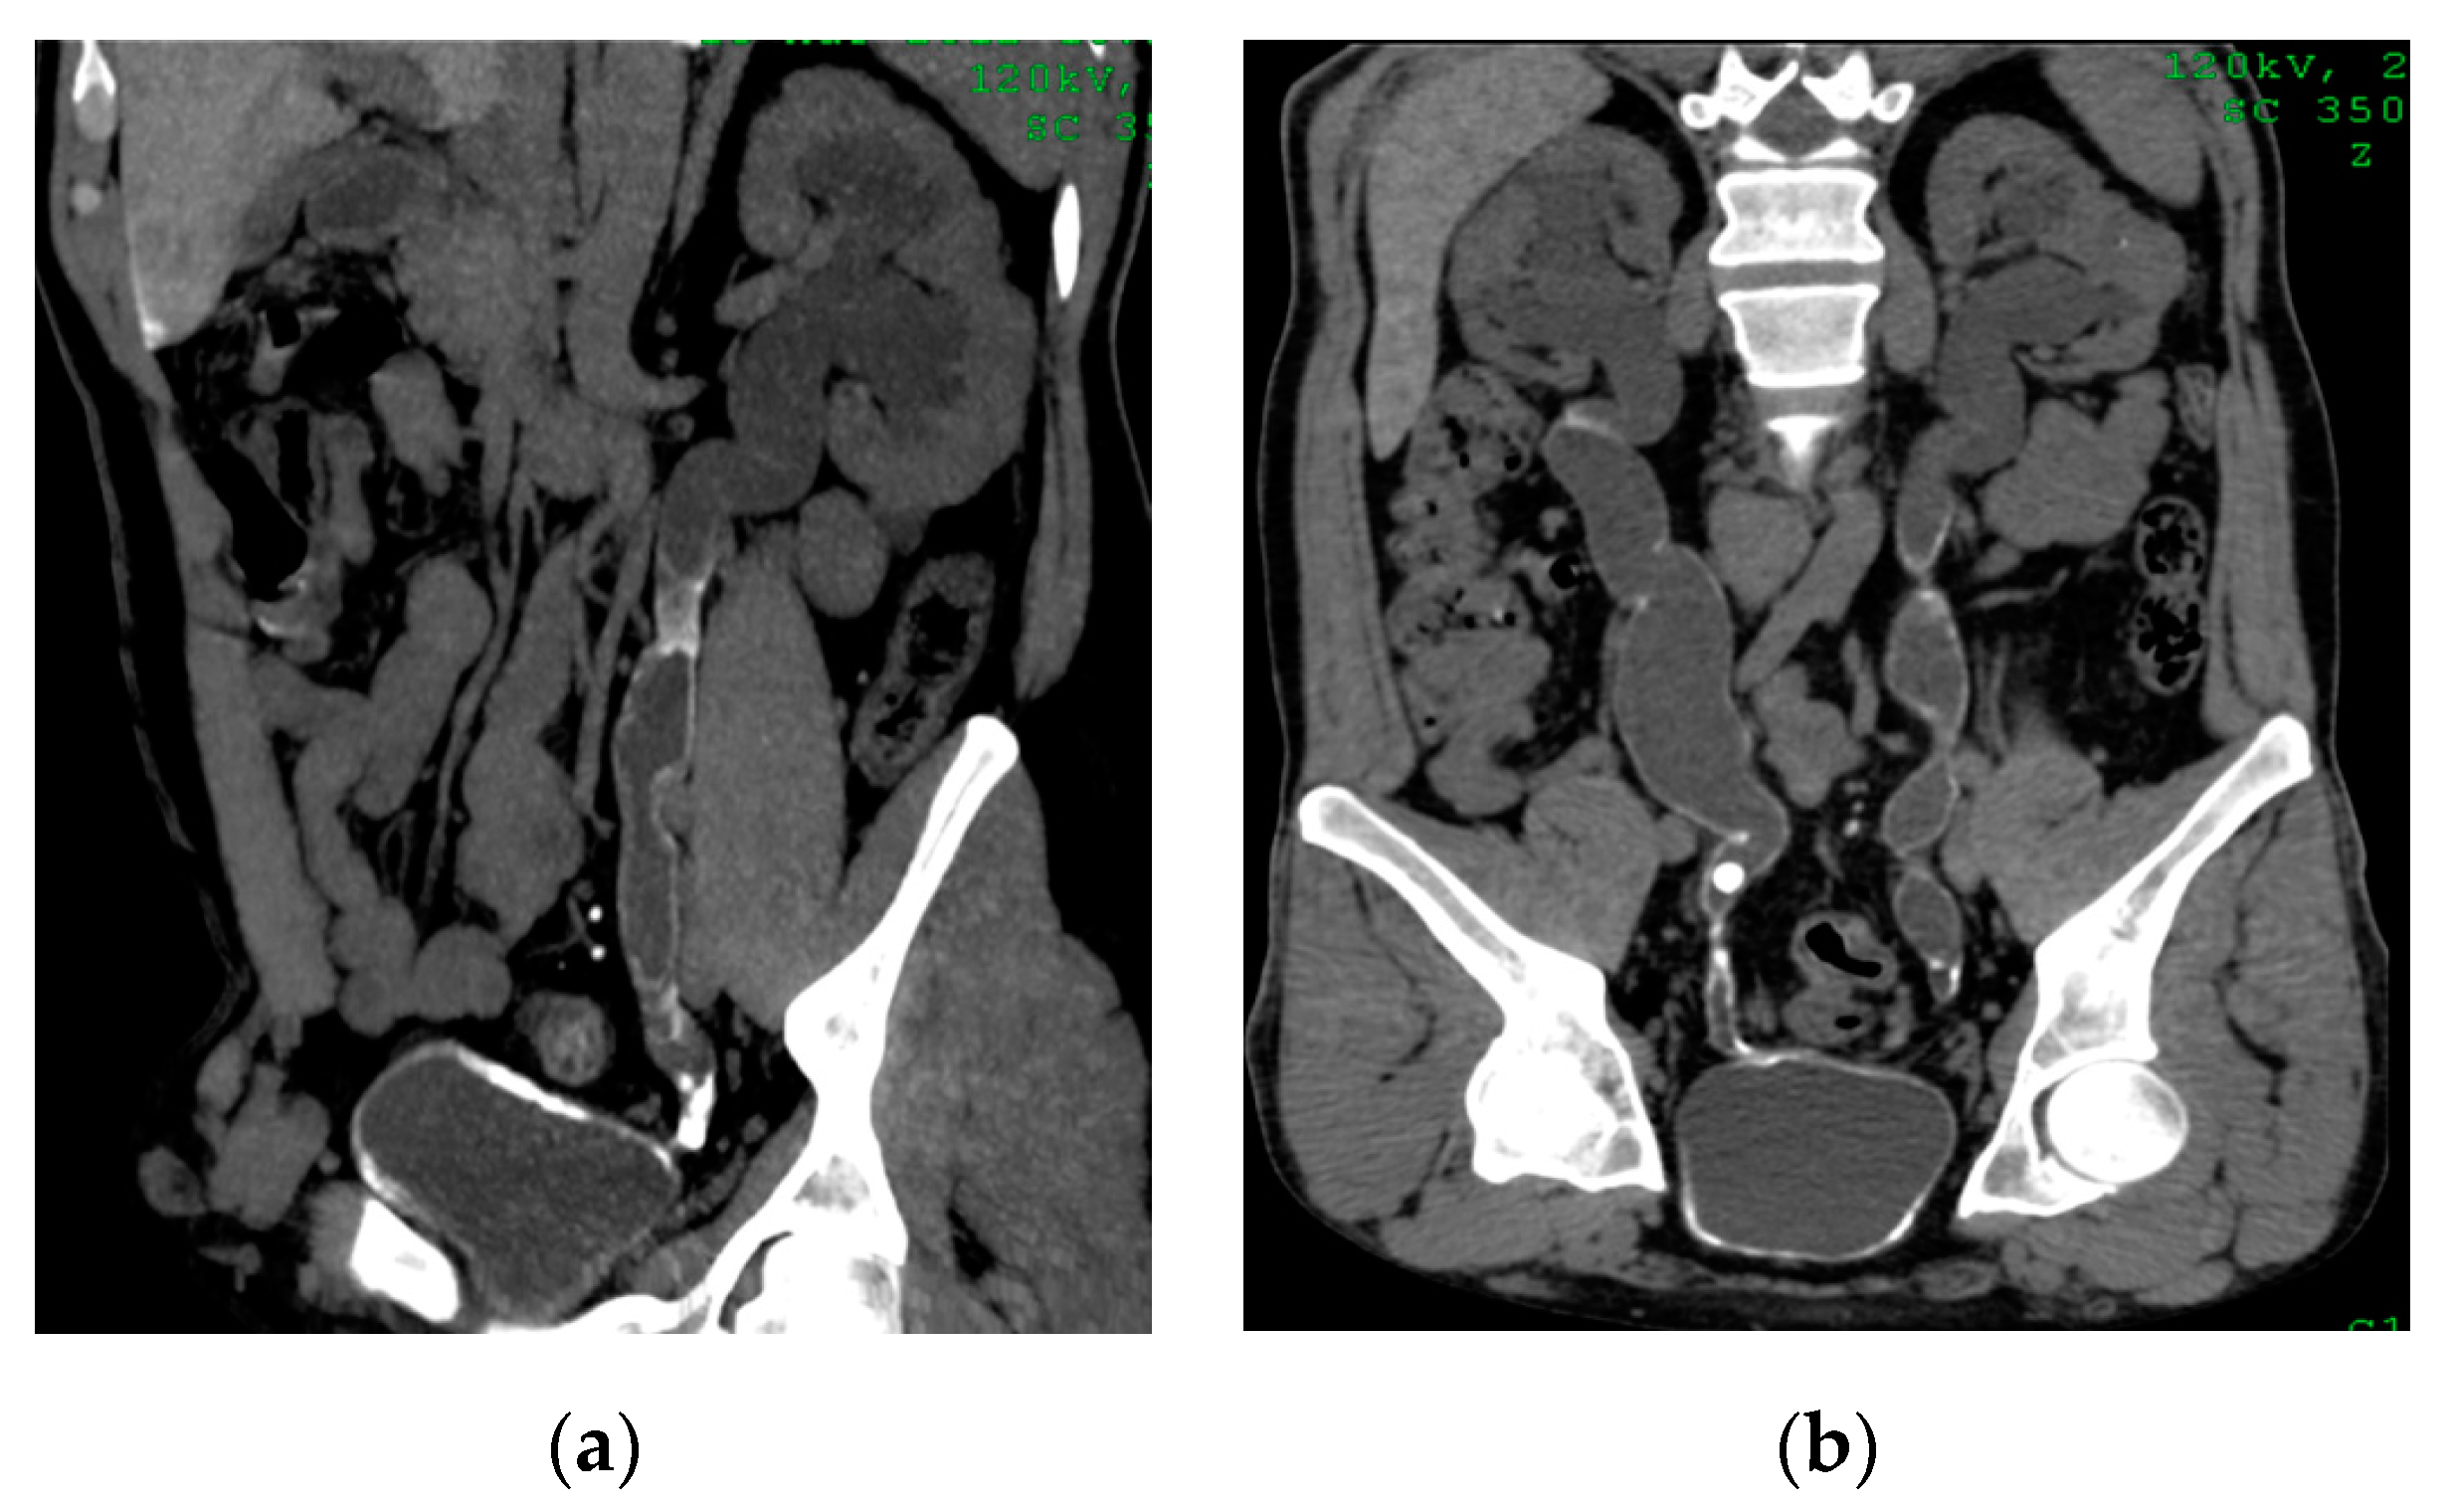

2.6. Emphysematous Urinary Tract Infection

| Emphysematous UTIs | Gas in the renal parenchyma, collecting system, bladder lumen and sometimes in the perirenal and perivesical tissue. |